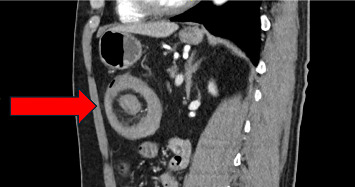

Abstract Image